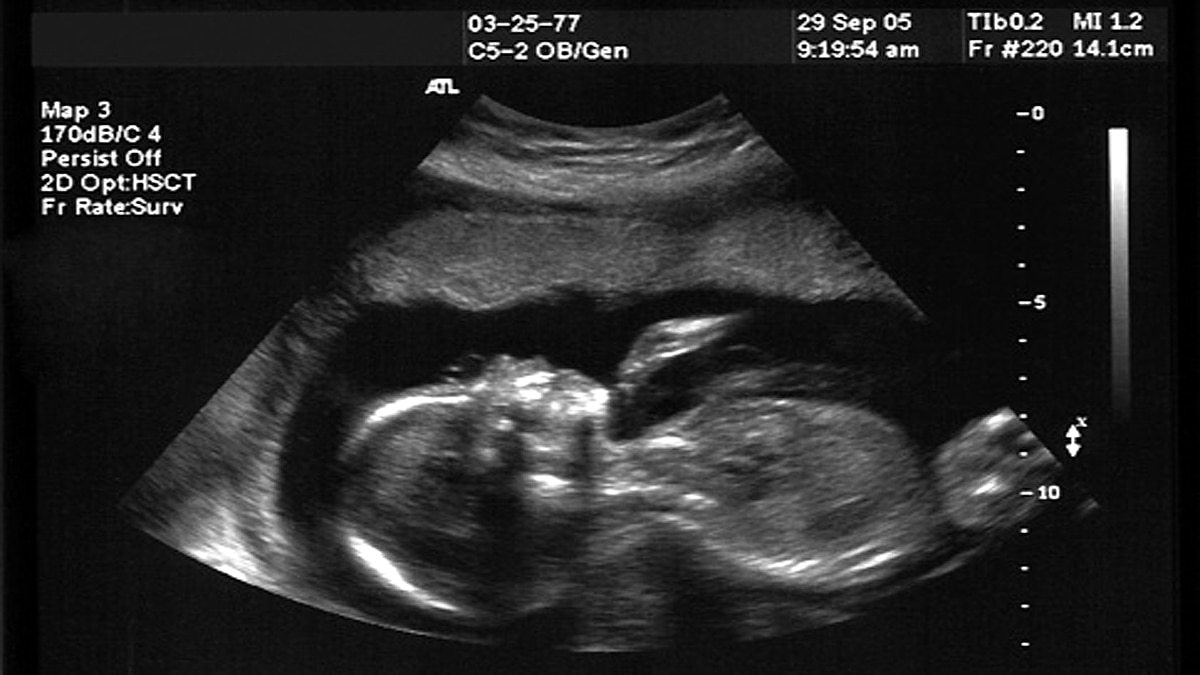

इस बात ने कई बार वैज्ञानिकों को महिलाओं के गर्भ की जांच करने की प्रेरणा दी. कई बार वैज्ञानिकों ने यूट्रेस (Uterus) और भ्रूण (Fetuses) की जांच की. जैसे साल 2005 में आर्काइव्स ऑफ डिजीस इन चाइल्डहुड एंड नियोनेटल एडिशन जर्नल में एक वीडियो फुटेज प्रकाशित किया गया था, जिसमें बच्चे की शक्ल का अल्ट्रासाउंड किया गया था. वह अलग-अलग तरह की भावभंगिमा बना रहा था. वह ऐसे एक्सप्रेशन दे रहा था, जैसे कि वह रो रहा है. यह बच्चा 33 हफ्ते की गर्भ में था. (फोटोः कैरोलिना मेडिकल सेंटर)

वैज्ञानिकों ने गर्भ के अंदर मौजूद बच्चे को कंपन और आवाज का सिमुलेशन दिया.  जैसे ही ये कंपन और आवाज बच्चे के पास तक पहुंची उसने अपने जबड़े चौड़े कर दिए. अपनी ठुड्डी को हाथ से छुआ, तीन बार लंबी सांस ली. उसका सीना फूलने लगा और सिर पीछे की तरफ लुढ़कने लगा. अंत में बच्चे की ठुड्डी पर कंपन महसूस की गई. डॉक्टरों ने करीब 60 बच्चों की स्कैनिंग की थी, जिसमें से 10 बच्चों ने इस तरह की हरकत की. ये हरकत तब होती है, जब बच्चे या कोई इंसान रोता है. निर्भर करता है कि आप रोने को कैसे परिभाषित करते हैं. सबके रोने का अलग-अलग तरीका होता है लेकिन आमतौर पर रोते समय यही प्रक्रिया होती है. (फोटोः नाद्जा रीसलैंड/Plos One)